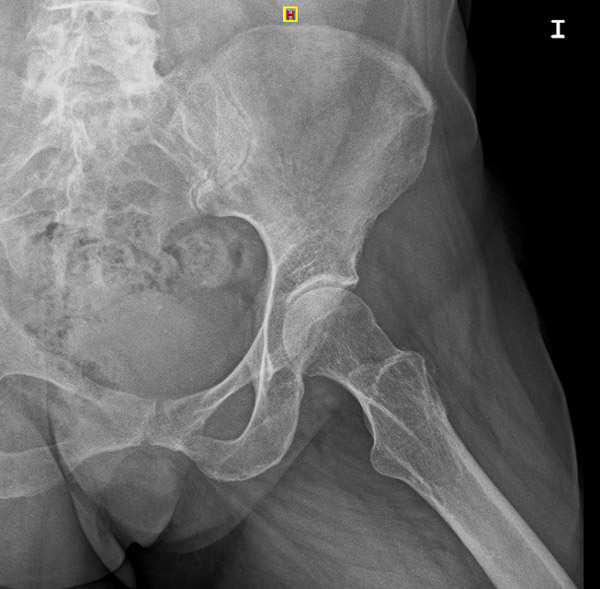

Pre-op X-rays

• Tonnis 1 Hip osteoarthritis ✔️

• Coxa profunda ✔️

• Femoroacetabular impingement Pincer type ✔️

• Anterior hip osteoarthritis ✔️